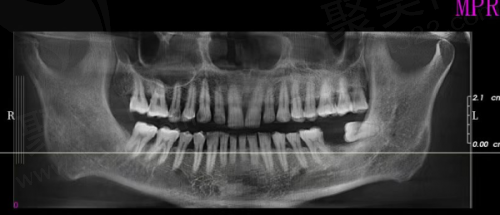

此外,并不是所有患者都适合这种方法。那些牙槽骨条件比较差、骨量不足的患者就不适合进行即拔即种。即使进行种植,骨结合的成效也可能不理想,导致种植体的松动和失败。

适合即拔即种植牙的患者需具备良好的口腔健康状况。具体来说,牙槽骨骨量充足的患者,且牙周组织健康,无重度牙周病或其他口腔疾病都可尝试这一技术。此外,对于那些迫切需要修复牙齿功能的人群,比如职业需要频繁与外界接触的销售人员或年轻的职场新人,在心理和功能上的需要驱动下,他们往往更倾向于选择即拔即种植。

与此同时,个性化的治疗方案制定也至关重要。在选择适合自己的种植方案之前,患者需要通过专精医生的评估,以确保自身条件符合即拔即种的要求。